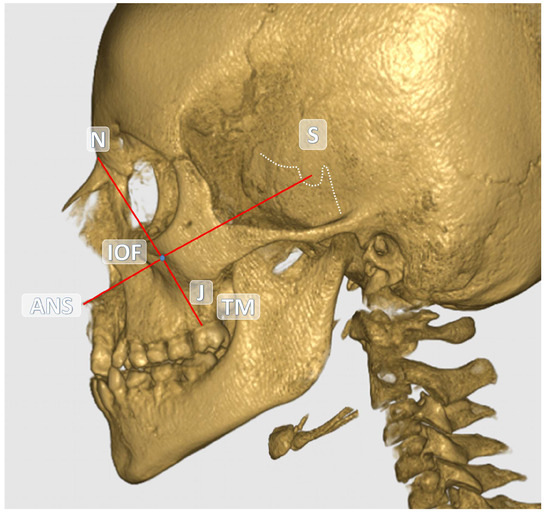

The central point of the infraorbital foramen (IOF) was used as the reference in all measurements. The anatomical landmarks used as references in the study are detailed in Table 1. All measurements were performed in millimeters (mm) based on CBCT images. The distances between the reference anatomical landmarks and the IOF are illustrated in Figure 1 and Figure 2. Additionally, the soft tissue thickness (STT) on the buccal side of the IOF was assessed using sagittal CBCT sections (Figure 3).

Figure 1. Coronal view of the IOF and other anatomical structures on the reconstructed CBCT image.

Figure 2. Sagittal view of the IOF and other anatomical structures on the reconstructed CBCT image.